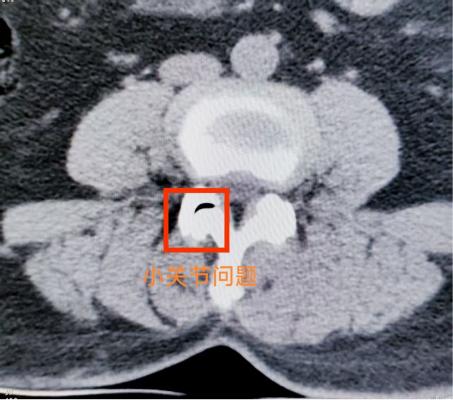

腰椎小关节增生紊乱:腰椎后方两侧成对的小关节,负责稳定脊柱并引导活动。它们如同门上的合页,一旦因劳损、退变导致软骨磨损、骨质增生,或发生微小错位,就会引发深层、定位模糊的腰痛。疼痛常在腰部扭转、后伸时加剧,有时晨起僵硬感明显。